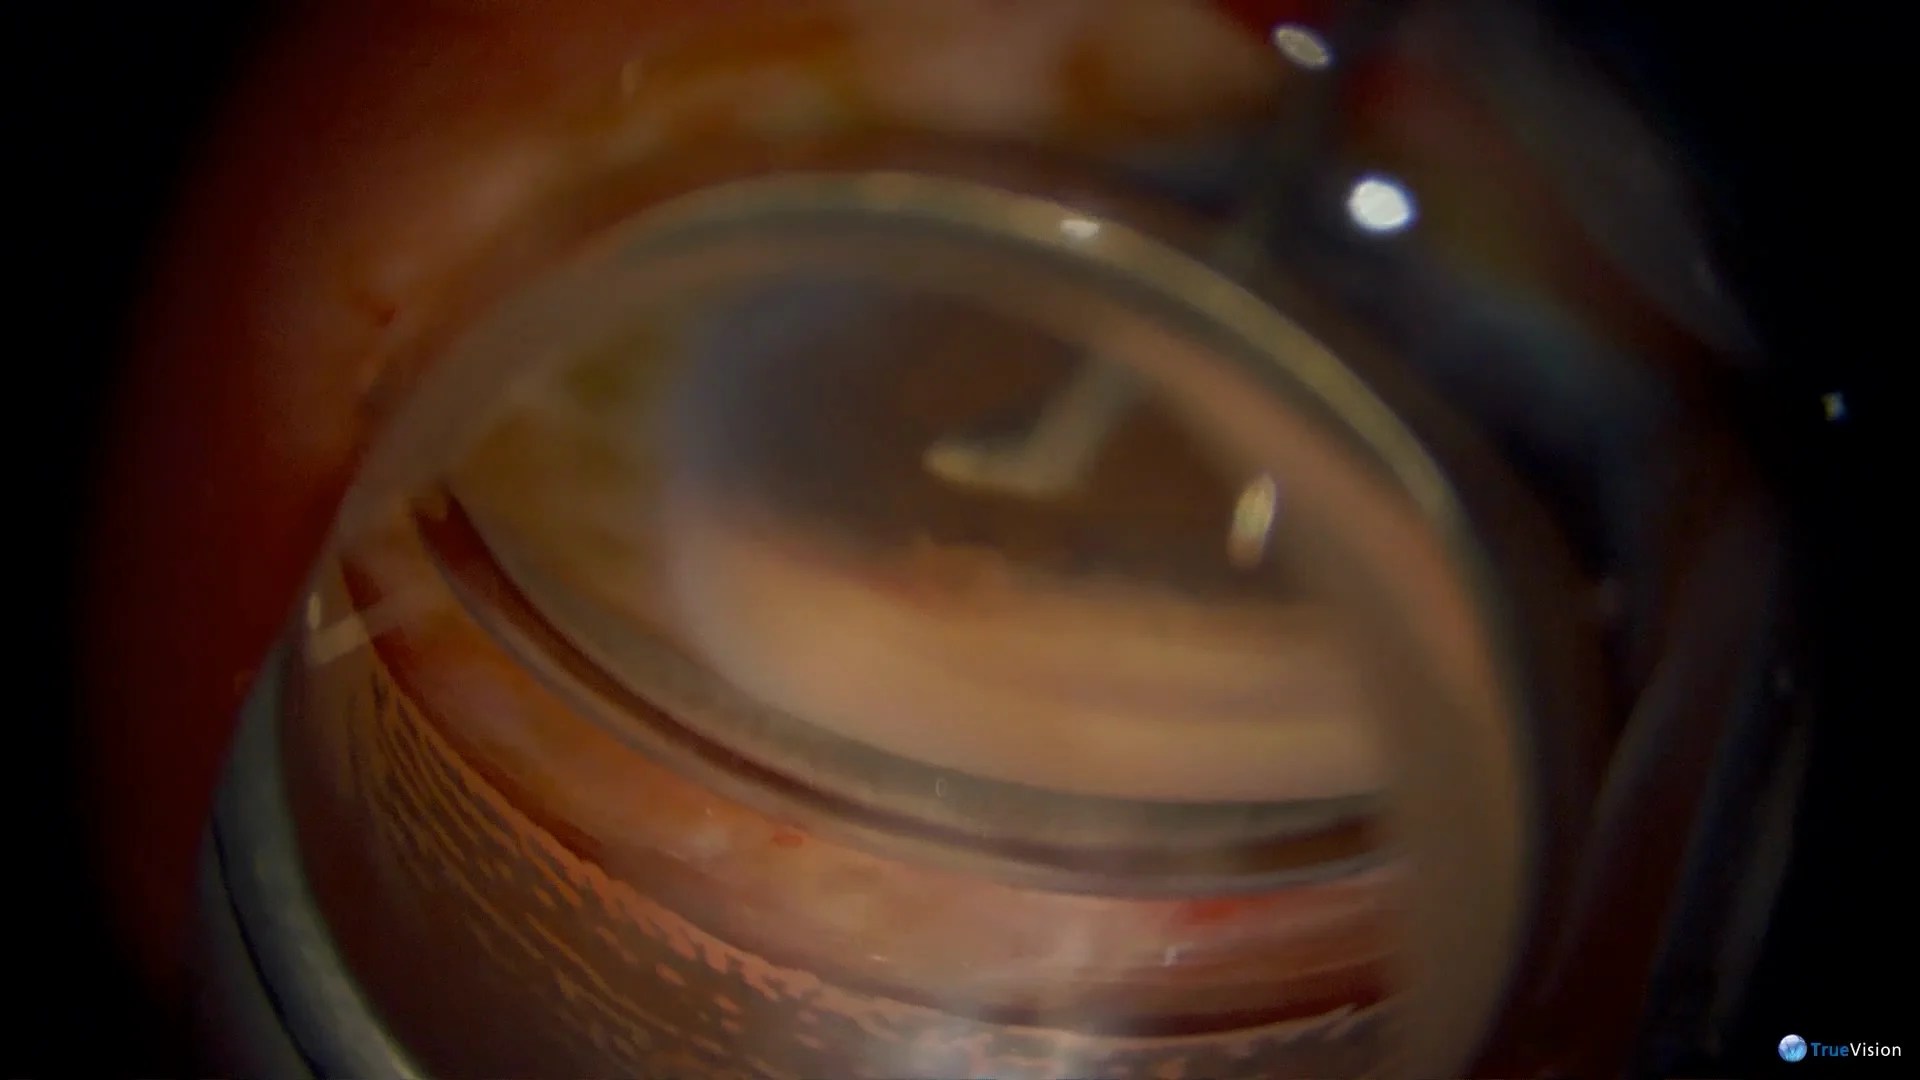

Procesos ciliares visibles con lente de gonioscopia de Goldmann de 3 espejos. : r/Ophthalmology